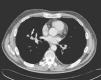

Case reportA 56-year-old man with a previous history of adenoid cystic carcinoma of the right maxillary sinus (pT4N0Mx) that had been treated by right radical hemimaxillectomy and radiotherapy 11 years earlier was admitted to our institution after referral from his oncologist. During the regular follow-up, a computed tomography (CT) scan showed a 2.5cm diameter nodule, with irregular morphology in the middle lobe, which was in contact with the middle lobe brochus and right inferior lobar artery (Fig. 1). A transbronchial biopsy with bronchoscopy was performed showing an epithelial neoplastic cell proliferation with large cytoplasms and hyperchromatic nuclei. Neoplastic cells expressed Cytokeratin AE1/AE3, Cytokeratin 7 and TTF-1. With these features, non-small cell carcinoma with immunohistochemical stigmas of adenocarcinoma was diagnosed. A positron emission tomography (PET) demonstrated a focus of increased FDG uptake in the right hilum contacting with the middle lobe.